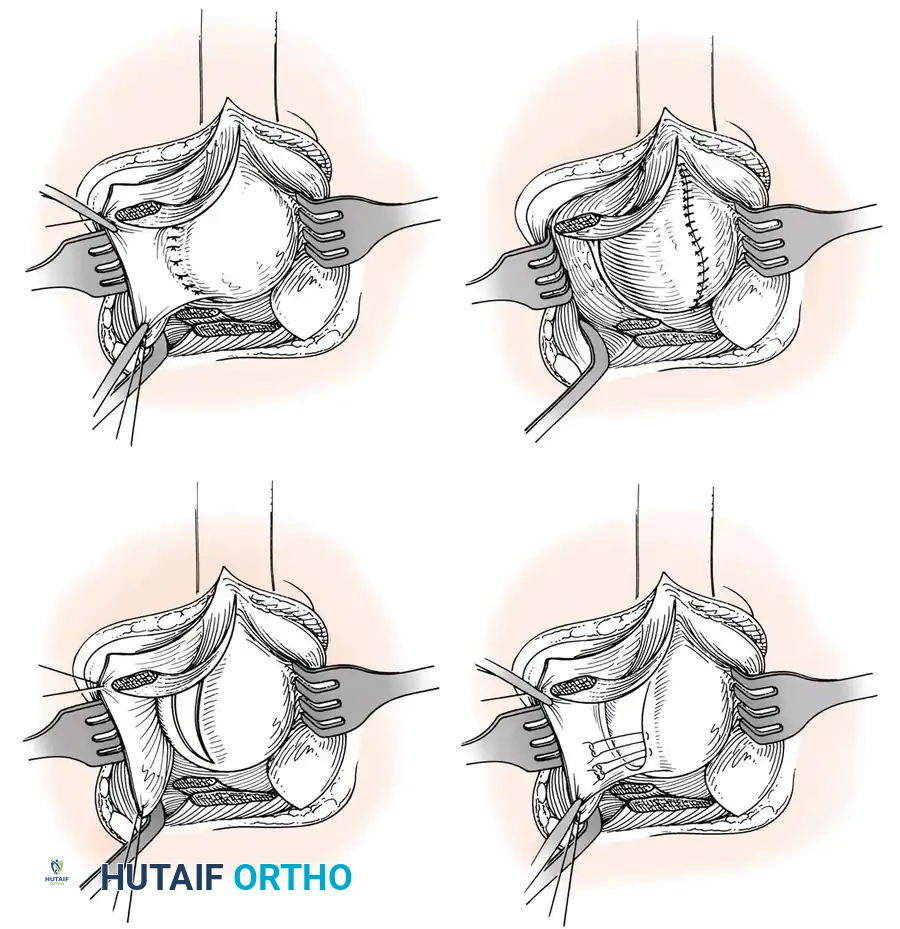

Glenoid Preparation and Labral Repair

The essential step in restoring stability is the anatomical reduction of the capsulolabral complex to a bleeding bone bed on the anterior glenoid rim.

- Debridement: The anterior glenoid neck is decorticated using a motorized burr, rasp, or osteotome to create a bleeding cancellous bed. This promotes robust biological healing of the repaired labrum.

- Mobilization: The scarred, medially displaced labrum (ALPSA lesion) must be fully mobilized using a periosteal elevator until the subscapularis muscle belly is visible anteriorly. The tissue must float freely to be shifted superiorly and laterally.

- Anchor Placement: Suture anchors (typically 3 to 4) are placed along the articular margin of the anteroinferior glenoid (from the 5:30 to 3:00 positions for a right shoulder). Anchors must be inserted at a 45-degree angle to the articular surface to maximize pullout strength and avoid joint penetration.

Capsular Shift and Closure

To address capsular redundancy, an inferior capsular shift is performed.

- The arm is positioned in 30 to 45 degrees of abduction and 20 degrees of external rotation.

- The inferior capsular flap is advanced superiorly and laterally, tensioning the IGHL complex. The sutures from the anchors are passed through the shifted capsule and tied.

- The superior flap is then brought down over the inferior flap in a "pants-over-vest" fashion to reinforce the anterior wall and close the rotator interval.

- The subscapularis split is loosely approximated with absorbable sutures. The deltopectoral interval is closed over a suction drain (if necessary), followed by routine subcutaneous and skin closure.